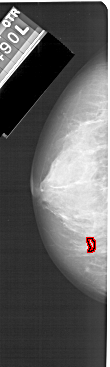

ics_version 1.0 filename A-1591-1 DATE_OF_STUDY 14 8 1990 PATIENT_AGE 52 FILM FILM_TYPE REGULAR DENSITY 4 DATE_DIGITIZED 7 1 1999 DIGITIZER HOWTEK 43.5 SEQUENCE LEFT_CC LINES 5131 PIXELS_PER_LINE 1531 BITS_PER_PIXEL 12 RESOLUTION 43.5 OVERLAY LEFT_MLO LINES 5386 PIXELS_PER_LINE 2011 BITS_PER_PIXEL 12 RESOLUTION 43.5 OVERLAY RIGHT_CC LINES 4651 PIXELS_PER_LINE 2011 BITS_PER_PIXEL 12 RESOLUTION 43.5 NON_OVERLAY RIGHT_MLO LINES 5296 PIXELS_PER_LINE 2206 BITS_PER_PIXEL 12 RESOLUTION 43.5 NON_OVERLAY |